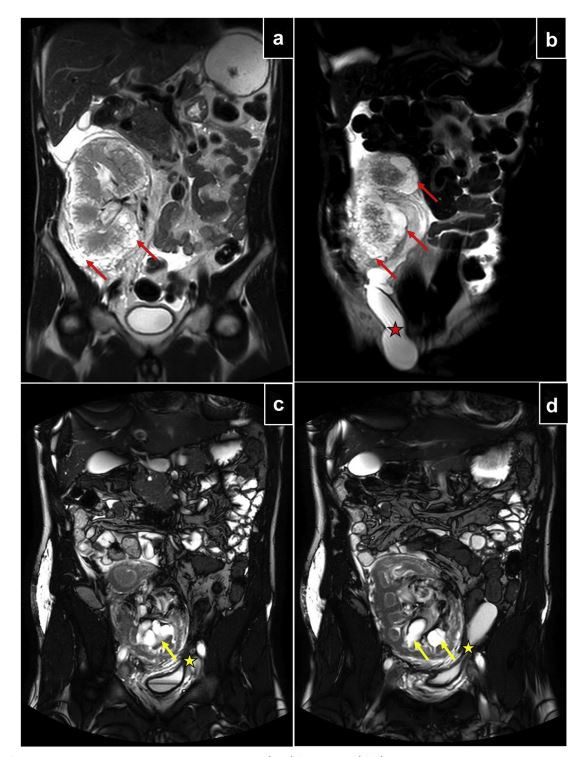

Un home de 34-anys va ser derivat al nostre departament per ascites refractària 10 anys després de la primeraronyótrasplantament per a malaltia renal terminal secundària a glomeruloesclerosi focal i segmentària idiopàtica. Havia experimentat un rebuig humoral subclínic agut demostrat per biòpsia revelat per l'aparició d'antígens específics del donant de nou 4 anys després del trasplantament. El rebuig es va tractar amb corticoides, immunoglobulines intravenoses i immunoadsorció (10 sessions). El nivell de creatinina sèrica es va mantenir estable a 0, 9 mg/dl, així com la relació albúmina-creatinina urinària a 50 mg/g. Després es va mantenir amb una combinació de tacrolimus, micofenolat de mofetil i esteroides. L'ascite va aparèixer gradualment 8 anys després del trasplantament, donant lloc a un malestar creixent. No hi va haver cap signe associat d'edema perifèric. La funció cardíaca era normal i no hi havia síndrome nefròtica. Les ascites eren transsudatives, no quiloses i sense evidència de malaltia infecciosa o maligna. La ressonància magnètica abdominal no va mostrar anomalies estructurals del fetge i la tomografia per emissió de positrons no va trobar cap evidència de càncer o malaltia limfomatosa. Tampoc hi havia signes de ganglis limfàtics retroperitoneals o fibrosi. També es va realitzar una biòpsia hepàtica i no va revelar cap anormalitat significativa. Tenint en compte la hipòtesi de la hiperplàsia nodular regenerativa induïda per micofenolats, que és possible que no es detecti en els resultats de la biòpsia, es va realitzar una conversió a l'objectiu de mamífers de l'inhibidor de la rapamicina (mTOR) (mTOR). La urografia per ressonància magnètica (urografia RM) va mostrar una nefromegàlia significativa (13, 7 cm, 603 ccs) amb múltiples col·leccions de líquid plurilocular perifèric als pols superior i inferior de l'empelt de ronyó, així com una àmplia ascites responsable de l'hidrocele inguinoscrotal (figures 1a i 1b). Es va realitzar una biòpsia d'empelt de ronyó i va revelar un rebuig humoral actiu crònic i un edema intersticial significatiu, però cap argument per al trastorn limfoproliferatiu posterior al trasplantament. Retrospectivament, el ronyó trasplantat tenia un aspecte normal en el moment de la obtenció sense detectar cap quist. No obstant això, 4 anys abans del recent episodi d'ascite (6 anys després del trasplantament), es va fer una ecografia per dolor intermitent a la zona de l'empelt: la seva mida ja havia augmentat (13 cm) i una quantitat important de líquid ({{23}). }} mm de gruix) va descriure l'empelt, que defensava la limfangiectàsia perirrenal (figura 2). Això ens va portar a concloure limfangiomatosi cortical i perirrenal. Un any després de la conversió de mTOR, el pacient va experimentar un millor control de l'ascite i l'alleujament del dolor, però el volum de l'empelt renal encara augmentava moderadament (14,3 cm, 654 cc). Pel que fa a la funció de l'empelt, el nivell de creatinina sèrica es va mantenir estable a 1,1 mg/dl. També es va proposar una cirurgia parietal protèsica sota el procediment de Lichtenstein per al tractament de l'hidrocele inguinoscrotal, però el pacient va preferir rebutjar la proposta.

Un home de 35-anys va ser derivat al nostre departament per dolor pèlvic crònic associat a símptomes urinaris 8 anys després del primer trasplantament de ronyó per malaltia renal terminal secundària a la síndrome hemolítica i urèmica infantil típica. Cinc anys després del trasplantament, va experimentar un rebuig humoral agut subclínic provat per biòpsia (biòpsia d'empelt realitzada a causa de l'antigen específic del donant de nou). Per tant, es va sotmetre a un tractament que combinava corticoides, immunoglobulines intravenoses i sis sessions d'intercanvi de plasma. El nivell de creatinina sèrica renal es va mantenir estable a 1,1 mg/dl, així com la relació albúmina-creatinina urinària a 32 mg/g. La teràpia immunosupressora de manteniment es basava en una combinació de tacrolimus, micofenolat de mofetil i esteroides. Davant la simptomatologia recent, es va realitzar una ecografia abdominal i es va trobar una nefromegàlia important (16 cm), associada a cavitats pielocaliceals normals, múltiples quists perifèrics, ascites perihepàtiques i perisplèniques. A l'exploració física, no hi havia signes d'edema perifèric. El company de la vena de l'empelt també es considerava turbulent. Es va realitzar una ressonància magnètica abdominal i no va trobar cap evidència de malaltia limfomatosa peritoneal, ganglis limfàtics retroperitoneals patològics o fibrosi. La venografia ilio-vena cava va descartar qualsevol estenosi venosa de l'empelt. Finalment, la RM-urografia i la RM-angiografia de l'empelt de ronyó van confirmar nefromegàlia important (8,5 - 12.{5 - 17 cm, 729 cc), múltiples quists parafilètics, limfangiectàsies pericapsulars i infiltració edematosa de greix perirrenal, tot el responsable de la compressió de la bufeta. Retrospectivament, en el moment del trasplantament, l'empelt renal mesurava 11,3 cm, sense cap quist. No s'havia descrit cap quist perifèric en el moment del trasplantament, ni en una altra ecografia realitzada 2 anys després. Quan es va realitzar una biòpsia d'empelt renal per diagnosticar el rebuig humoral agut subclínic 3 anys després del trasplantament, la mida del ronyó era de 13,5 cm. A partir del resultat d'imatge (especialment RM-urografia), es va fer el diagnòstic de limfangiomatosi d'empelt renal amb un desenvolupament perihilar específic (figures 1c i 1d) i es va canviar el micofenolat de mofetil a mTOR. Tot i que l'ascite es va controlar millor, la mida de l'empelt va augmentar significativament 6 mesos després (8,5 - 13.5 - 18 cm, 910 cc). Aleshores es va retirar mTOR i es va reiniciar el micofenolat de mofetil. Tres mesos després, el volum de l'empelt renal va disminuir parcialment (17 cm, 770 cc) però l'ascite va tornar a aparèixer.